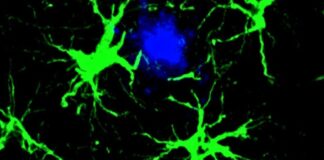

Вчені зменшили амілоїдні бляшки на 50% у мишей за допомогою сконструйованих...

Інженерні клітини зменшили амілоїдні бляшки у мишей на 50%, демонструючи перспективність у боротьбі з хворобою Альцгеймера

Дослідники з Вашингтонського університету досягли значного прориву у...